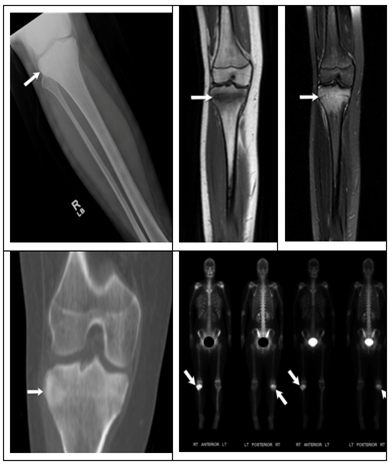

Figure 2 Patient 2 imaging review.

1. Figure 2A: AP view X-ray of pelvis showing a sclerotic left iliac lesion.

2. Figure 2B: Axial CT demonstrating sclerotic left iliac lesion.

3. Figure 2C: T2 MRI of the pelvis demonstrating left iliac cortical sclerosis and underlying bone marrow edema.

4. Figure 2D: AP view X-ray of the right clavicle showing increased sclerosis. Findings consistent with multifocal CNO in the same patient.

5. Figure 2E: MRI of the clavicle showing cortical sclerosis and bone marrow edema.